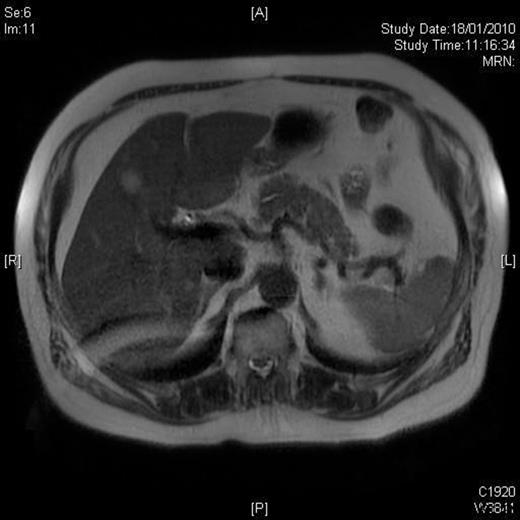

The operative time was 50 minutes and the blood loss was less than 20 ml. The patient made an uneventful recovery and was discharged on the second postoperative day. Histology demonstrated complete excision of a LCA with no cell atypia. A 3-month postoperative MRI showed no disease recurrence and normal appearance of the splenic remnant [Figure 3].